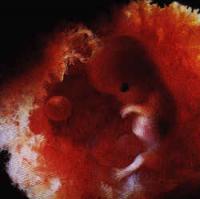

А вот на этом какое?

Это не УЗИ. Это фотоснимок. Очень опасная процедура, так как идет вмешательство в матку. Видела в фильме о беременности, как вводили этот датчик и рассматривали ребеночка, его ручки, глазики... Не понимаю, зачем такое делают... ученые

мне показалось, что это снимок, что-то вроде тех, что делаются так же, как и фильмы снимают про внутриутробное развитие. но если у кого-то есть такое узи, тогда я не знаю.но знать мне тоже хотелось бы